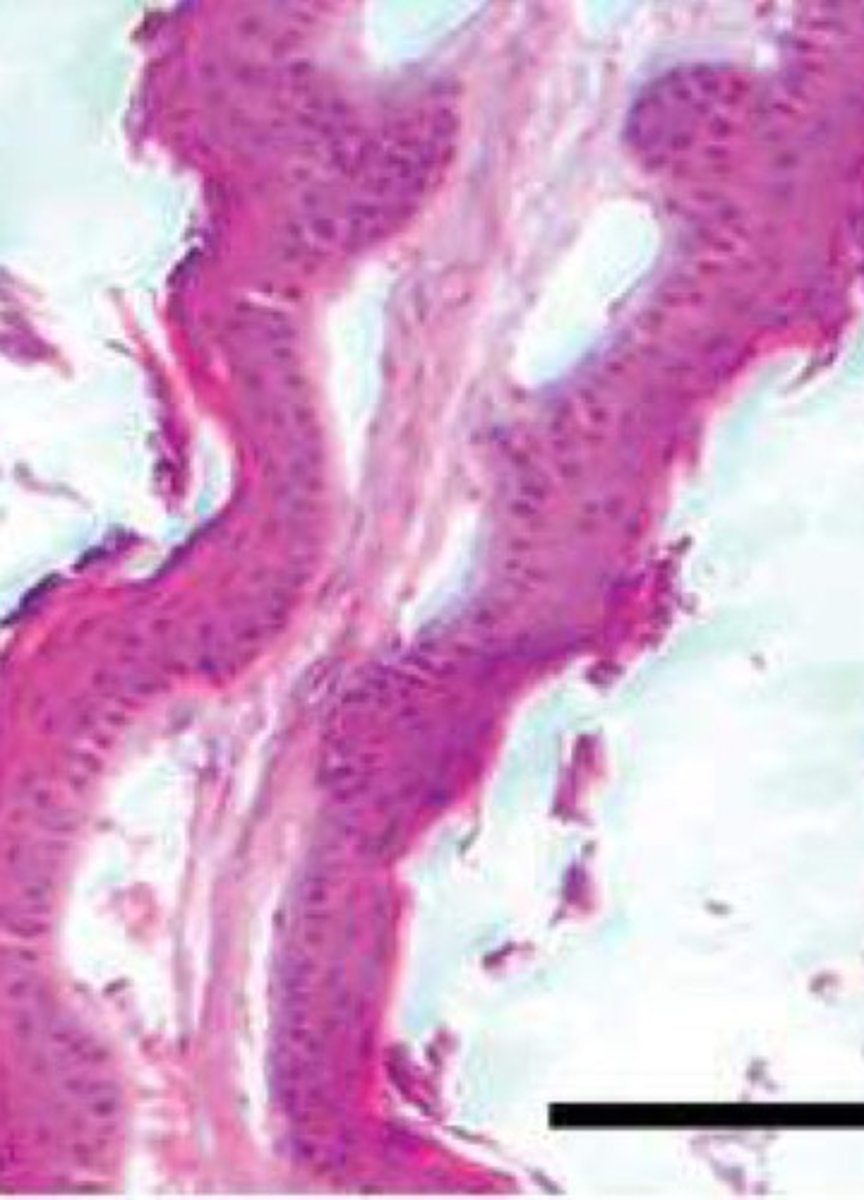

Rumen _____ & ______ increase in size with lactation due to high energy demand to allow for better absorption

Mass, papillae

Increase in papillae during lactation will allow for greater ______ metabolism and may be a result of _____ receptors responding to SCFAs

Butyrate, nuclear